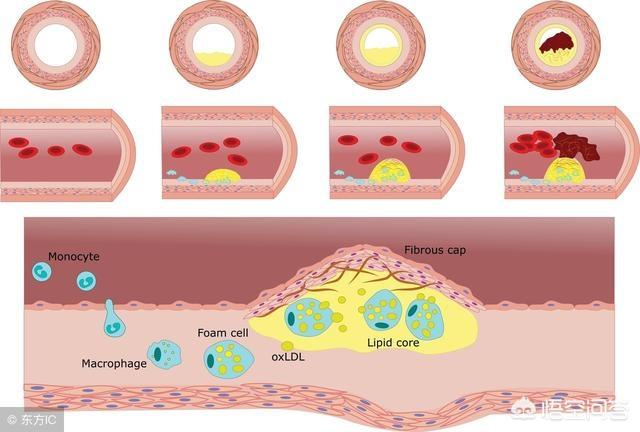

高脂血症などの心血管危険因子の影響により、血管の内壁は徐々に傷つき、血液中の余分な脂質は徐々に血管壁の下に沈着し、黄色い粥腫性脂質コアを形成し、最終的には脂質コアに線維性被膜が形成され、これが動脈プラークの形成過程である。 プラークは動脈硬化を引き起こす危険因子であり、安定性や破裂に問題のあるプラークは、反応性血小板血小板の反応性凝集は血栓を形成し、動脈血管を閉塞させ、梗塞性心血管病を引き起こすことさえある。したがって、私たちはプラークの問題に注意を払う必要がありますが、通常、すでに形成されたプラークを元に戻したり除去したりすることは非常に困難であり、私たちがしなければならないことは、合理的な薬物療法と運動によってプラークの形成を予防し、既存のプラークに対して、プラークの安定性を維持するように努め、動脈硬化のプロセスを遅らせ、プラークの破裂がより大きなリスクを引き起こすのを防ぐことです。

プラークは、静脈プラーク、動脈プラークを持って、それは複数の病因因子の役割にある、沈殿物の脂質化のために、単刀直入に言えば、つまり、あなたがより多くのグリース、消化と使用することはできません、血中脂質4と他の多因子の影響下で、内膜に損傷を与え、血管の内層に沈着し、黄色のアテローム性脂質のコアの形成、および最終的に線維性キャップが持続的な炎症にさらされている場合、通常は非常に安定している脂質のコア、上の線維性コアの形成にある攻撃は、飲酒、怒り、夜更かし、少ない水を飲むなど、線維性キャップが破裂し、プラークが流出し、血液中の血小板が結婚フラッシュ、血栓と呼ばれるトラブルメーカーの子供を出産し、この子は、血管をブロックするために悪いことをすることに特化し、トラブルを作るためにさまよう、血管の内腔に血栓が同時に狭くなるだけでなく、破裂、急性心脳血管イベント、脳卒中、心筋梗塞、肺塞栓症、腎不全、静脈瘤などを誘発する。などである。したがって、プラークを除去することは、血管の詰まりを取り除くだけでなく、急性心血管系および脳血管系イベントを予防することにもなり、誰もが関心を寄せている。

動脈プラークは、複数の病因因子の影響下にある動脈内膜の損傷によって引き起こされる一連の炎症反応であり、後に二次的なアテローム性プラークが生成される。プラークの形成は人体にとってより有害であり、同時に血管の内腔を狭くし、破裂して急性心血管系イベントを誘発することもある。したがって、プラークを除去することは血管の詰まりを解消するだけでなく、急性心血管系イベントを予防することにもなり、これはすべての患者の心臓の鼓動である。プラークの治療には、血中脂質、血圧、血糖値などのコントロール、減塩、低コレステロール食、運動量の増加、禁煙、アルコール制限などの悪い生活習慣の改善など、病気の原因から始めるか、上記の治療の上に薬物療法を行うことができます。薬の選択は、アトルバスタチン、レセルプルバスタチンなどのスタチン系薬剤がアテローム性プラークの治療によく使用されます。具体的な治療計画は専門医の指導のもとに立てるべきである。

プラークが発生する過程にはいくつかの段階があり、まず血管の内皮が傷つき、血管内面の保護層が「壊れる」ようになると、血液中の高分子脂肪が低比重リポ蛋白と呼ばれる一種の物質によって血管壁の内膜中膜層に大量に運ばれて蓄積し、血管壁が肥厚し、医療では内膜中膜層が1mm以上になると動脈硬化が起こっていると言われています。内膜中膜層の肥厚が1mmを超えると、局所的に凝集して塊になったような動脈硬化、すなわち初期プラークが生じたといわれる。

初期のプラーク形成は、脂肪の蓄積が一連の炎症反応を引き起こし、実際には、脂肪は常に酸化変性、粥状物質の形成であり、これらの物質は、血管の正常な構造を破壊し、血管の一部となり、この時点で、脂質化された材料は、通常、ソフトスポットと呼ばれる液体の状態にほとんどである。

ソフトスポットの脂質化した物質は、皮膚感染症が膿を出すと線維化し痂皮化するように、時間の経過とともに壊死することがある。また、カルシウムが沈着すると石灰化が起こり、プラークが硬くなり、血管収縮機能がより低下する。このようなプラークはハードスポットと呼ばれる。

プラークが血管に与えるダメージや影響は、プラークの形成段階によって異なることがわかる。 初期のプラークは血管の構造に深刻なダメージを与えておらず、除去したり元に戻したりできる可能性があるが、ソフトプラークやハードプラークはすでに血管の正常な構造を置き換えてしまっている。プラークを完全に除去することは不可能であり、プラークの継続的な成長を止め、遅らせることが必要である。